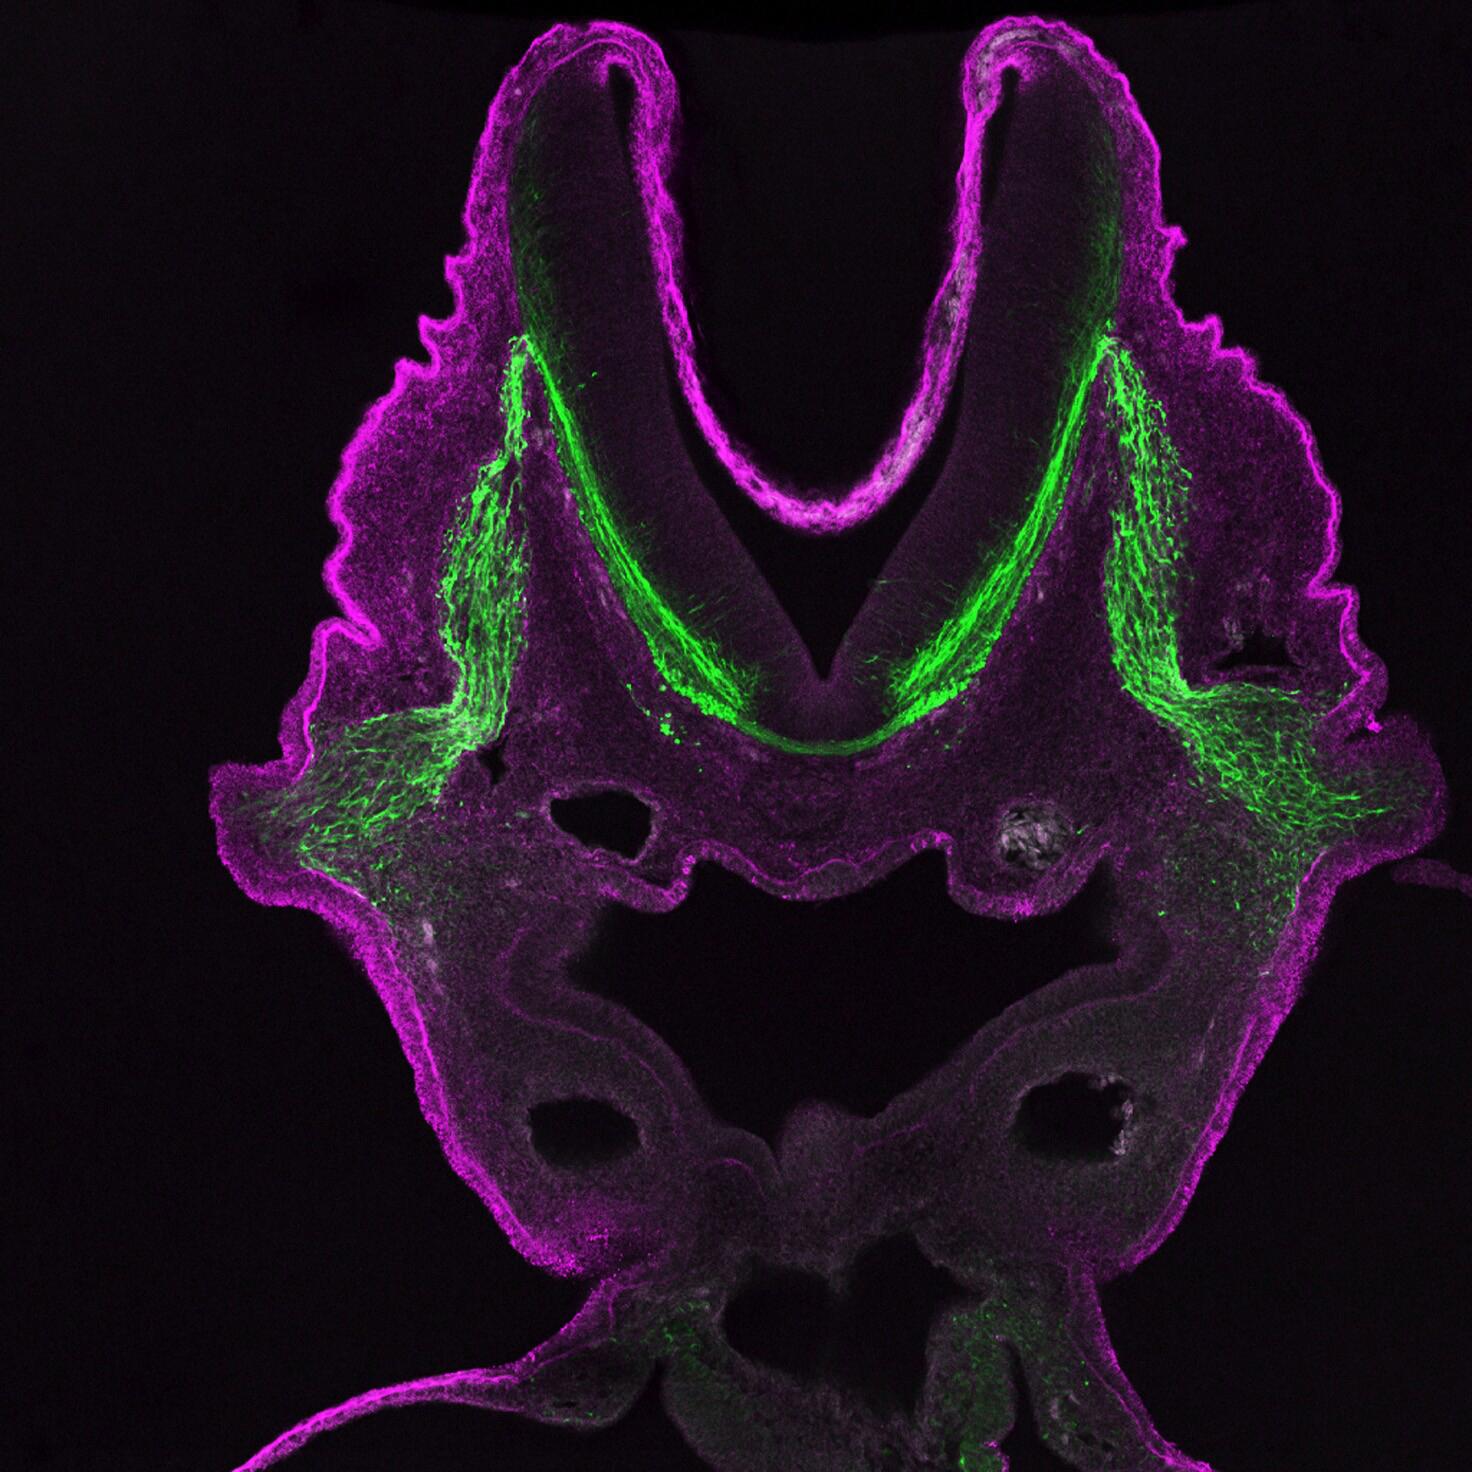

Confocal microscopes

Unlike other light microscopes which create an image focused at a single distance (z-plane), a confocal microscope uses a laser to scan multiple z-planes. Upon scanning acquisition of different individual z-planes, a three-dimensional image can be created by a computer.

Given the ability of confocal microscopy to generate a three-dimensional image, researchers recently have applied this technique to image tuberculosis infected lungs to monitor antibiotic uptake. A challenge in treating tuberculosis is the antibiotics must reach and enter every infected cell to be effective. Therefore being able to see where antibiotics travel within the lung space contributes to our understanding of current antibiotics and informs future therapeutic developments.